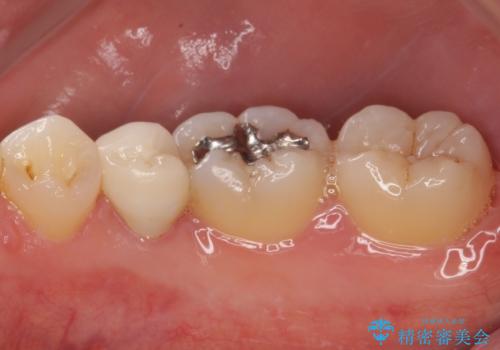

患者様と相談の上、再根管治療を行い、その後オールセラミッククラウンにて補綴治療を行うこととしました。

治療について

根管治療後9ヶ月で撮影したレントゲン写真より、歯根周辺の透過像が十分に消失している様子が認められました。